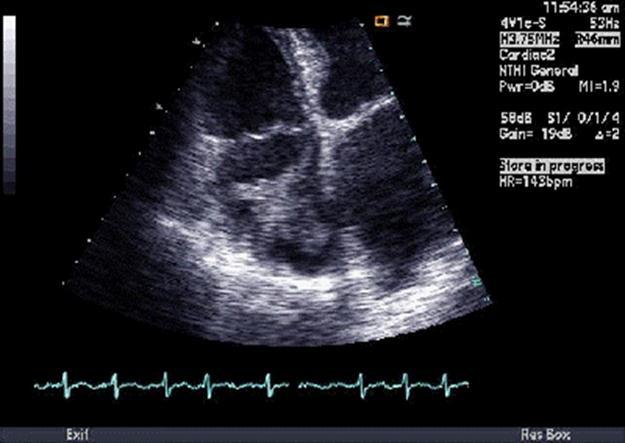

87 year old female from nursing home was admitted to Coronary Care Unit (CCU) because of atrial fibrillation with rapid ventricular rate. Heart rate was controlled with digoxin and metoprolol and continued on warfarin. Echocardiogram showed a highly mobile right atrial thrombus (Figure 2), left ventricular ejection fraction 40-45%. Six days later, echo and magnetic resonance imaging (MRI) did not show the thrombus; however, CT of the chest showed emboli in the pulmonary arterial branches of the right middle and right lower lobes. Venous duplex showed acute deep venous thrombosis in the right leg. No ABG was done. Blood analyses showed glucose 99, BUN/Cr 15/0.5, Na 137, K 3.4, Ci 107, bicarbonate 24, Ca 8.4, albumin 2.2, three sets of cardiac enzymes (CKMB & CTNI) within normal limits, WBC 7.6, hemoglobin 9.2, hematocrit 27, platelets 134, fecal occult blood negative. Inferior vena cava (IVC) filter was placed under fluoroscopic guidance before discharging the patient on digoxin and warfarin.

Figure 2.Echographic image of Case 2 of the large, mobile thrombus in the right atrial cavity.